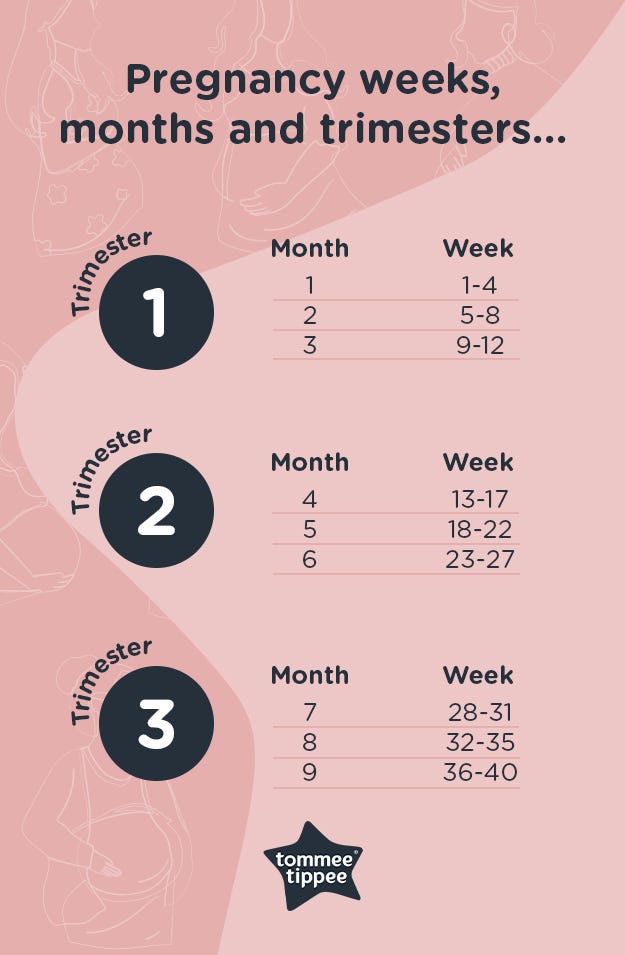

Week By Week Pregnancy Symptoms Tips Advice Guide 1st Trimester

Trimesters In Pregnancy Chart

Trimesters In Pregnancy Chart